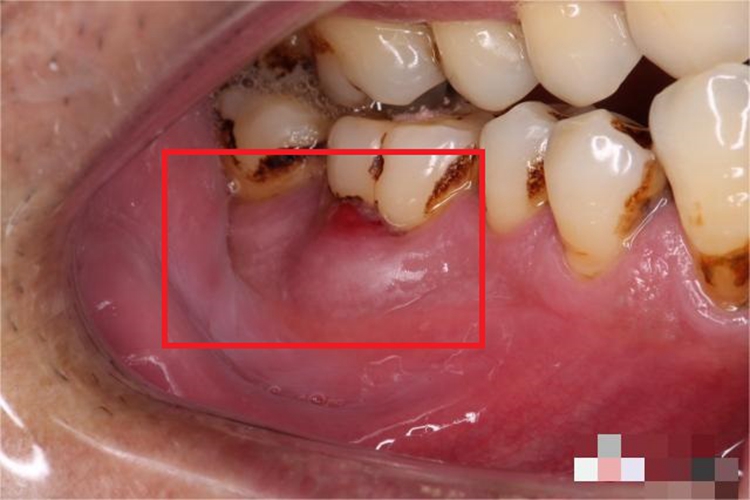

急性牙周脓肿的患者牙龈处可见凸起的肿块,表面发亮,颜色发红,患者自觉疼痛。

急性牙周脓肿可累及牙龈部位,表现为椭圆形或半球状凸起的肿块,表面发亮且颜色发红,同时牙龈可出现发红、水肿、出血等异常表现,自觉有搏动性疼痛。